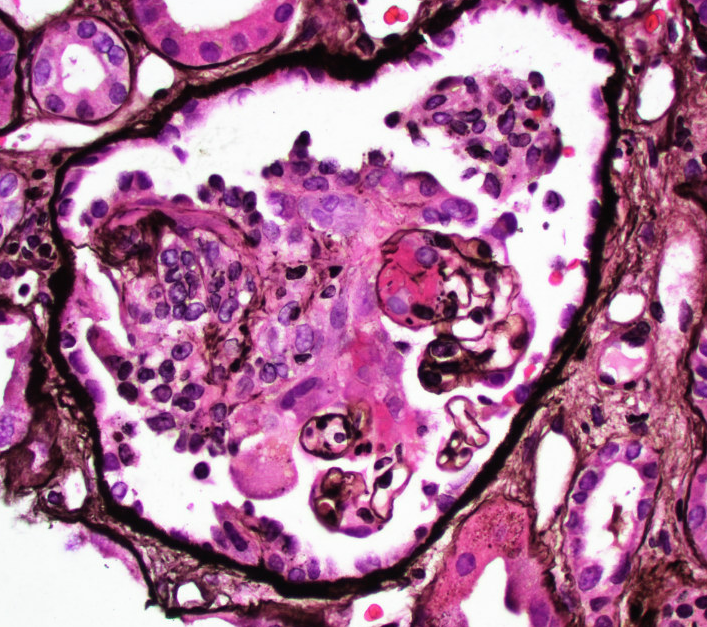

Mini case-series of crystal-storing histiocytosis (CSH) affecting predominantly glomerular loops with detailed literature review of renal CSH, images of one of the cases are depicted below, authors.elsevier.com/c/1Zh4S3uV~y8B…